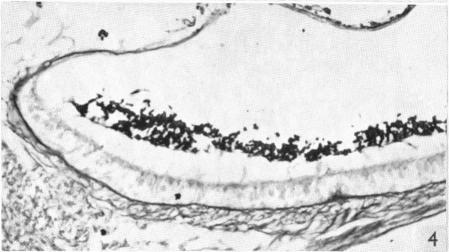

Selective and histochemical staining of the otolithic membranes, cupulae and tectorial membrane of the inner ear.

J Anat. 1955 Jan;89(1):3-12.